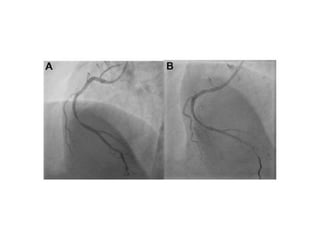

Contro lateral injection to check

guide wire position in true lumen Final Result